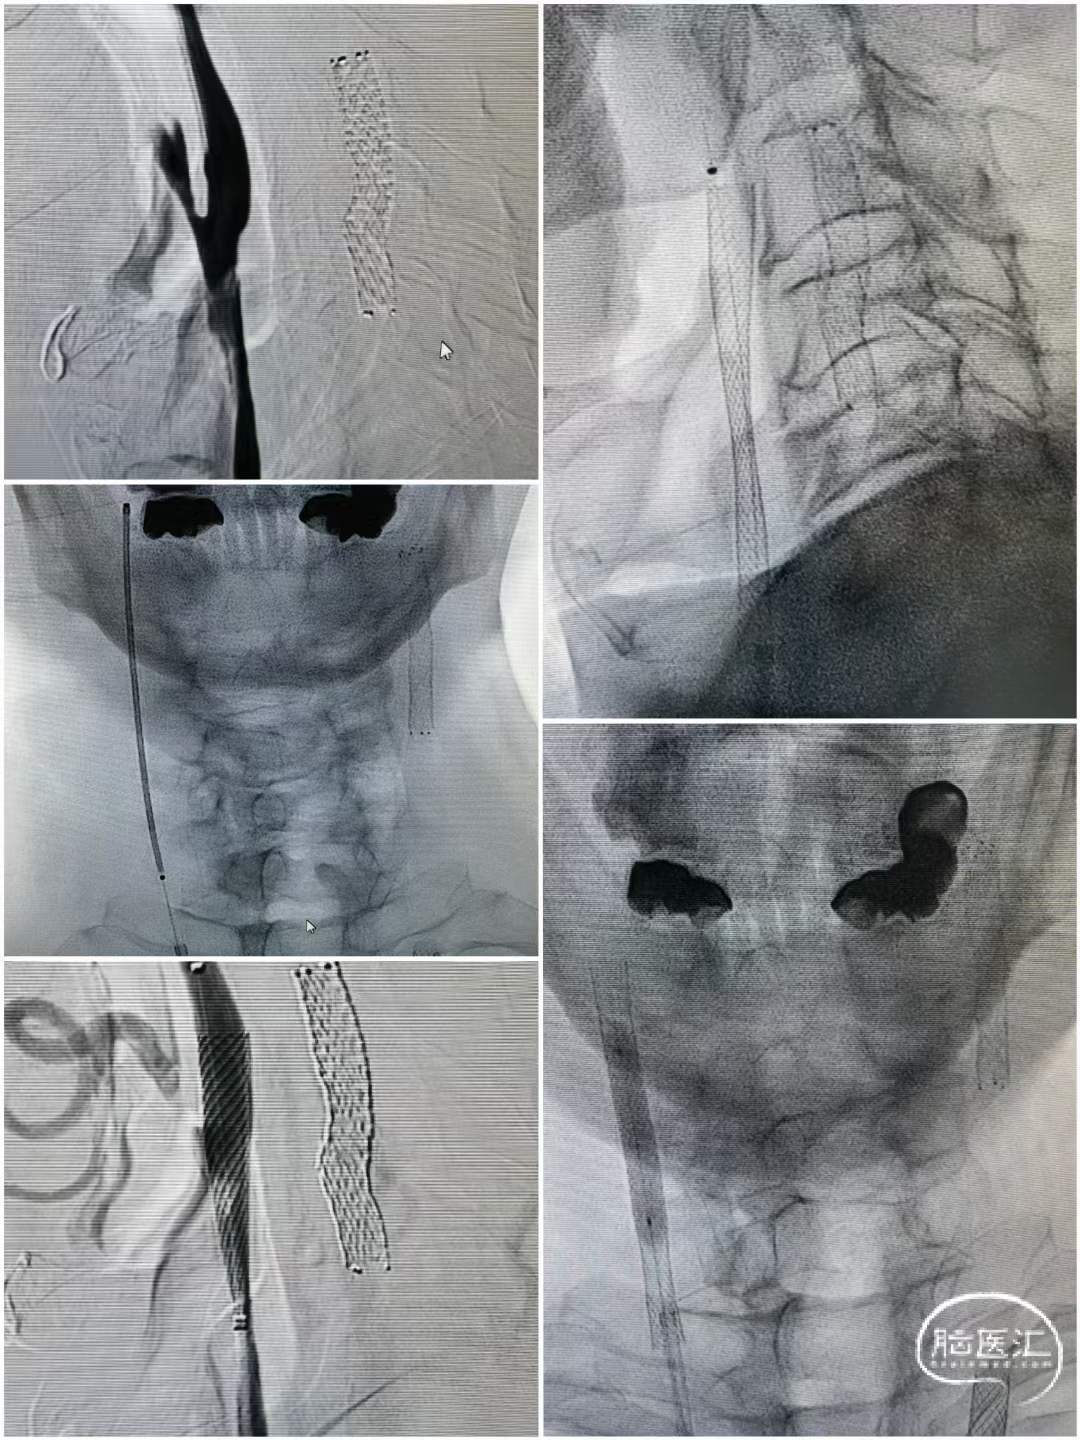

术中操作

左侧串联病变处理

跨越狭窄段释放支架,造影可见左侧狭窄明显改善。

右侧慢性闭塞处理

跨越狭窄段释放支架,造影可见右侧闭塞再通。